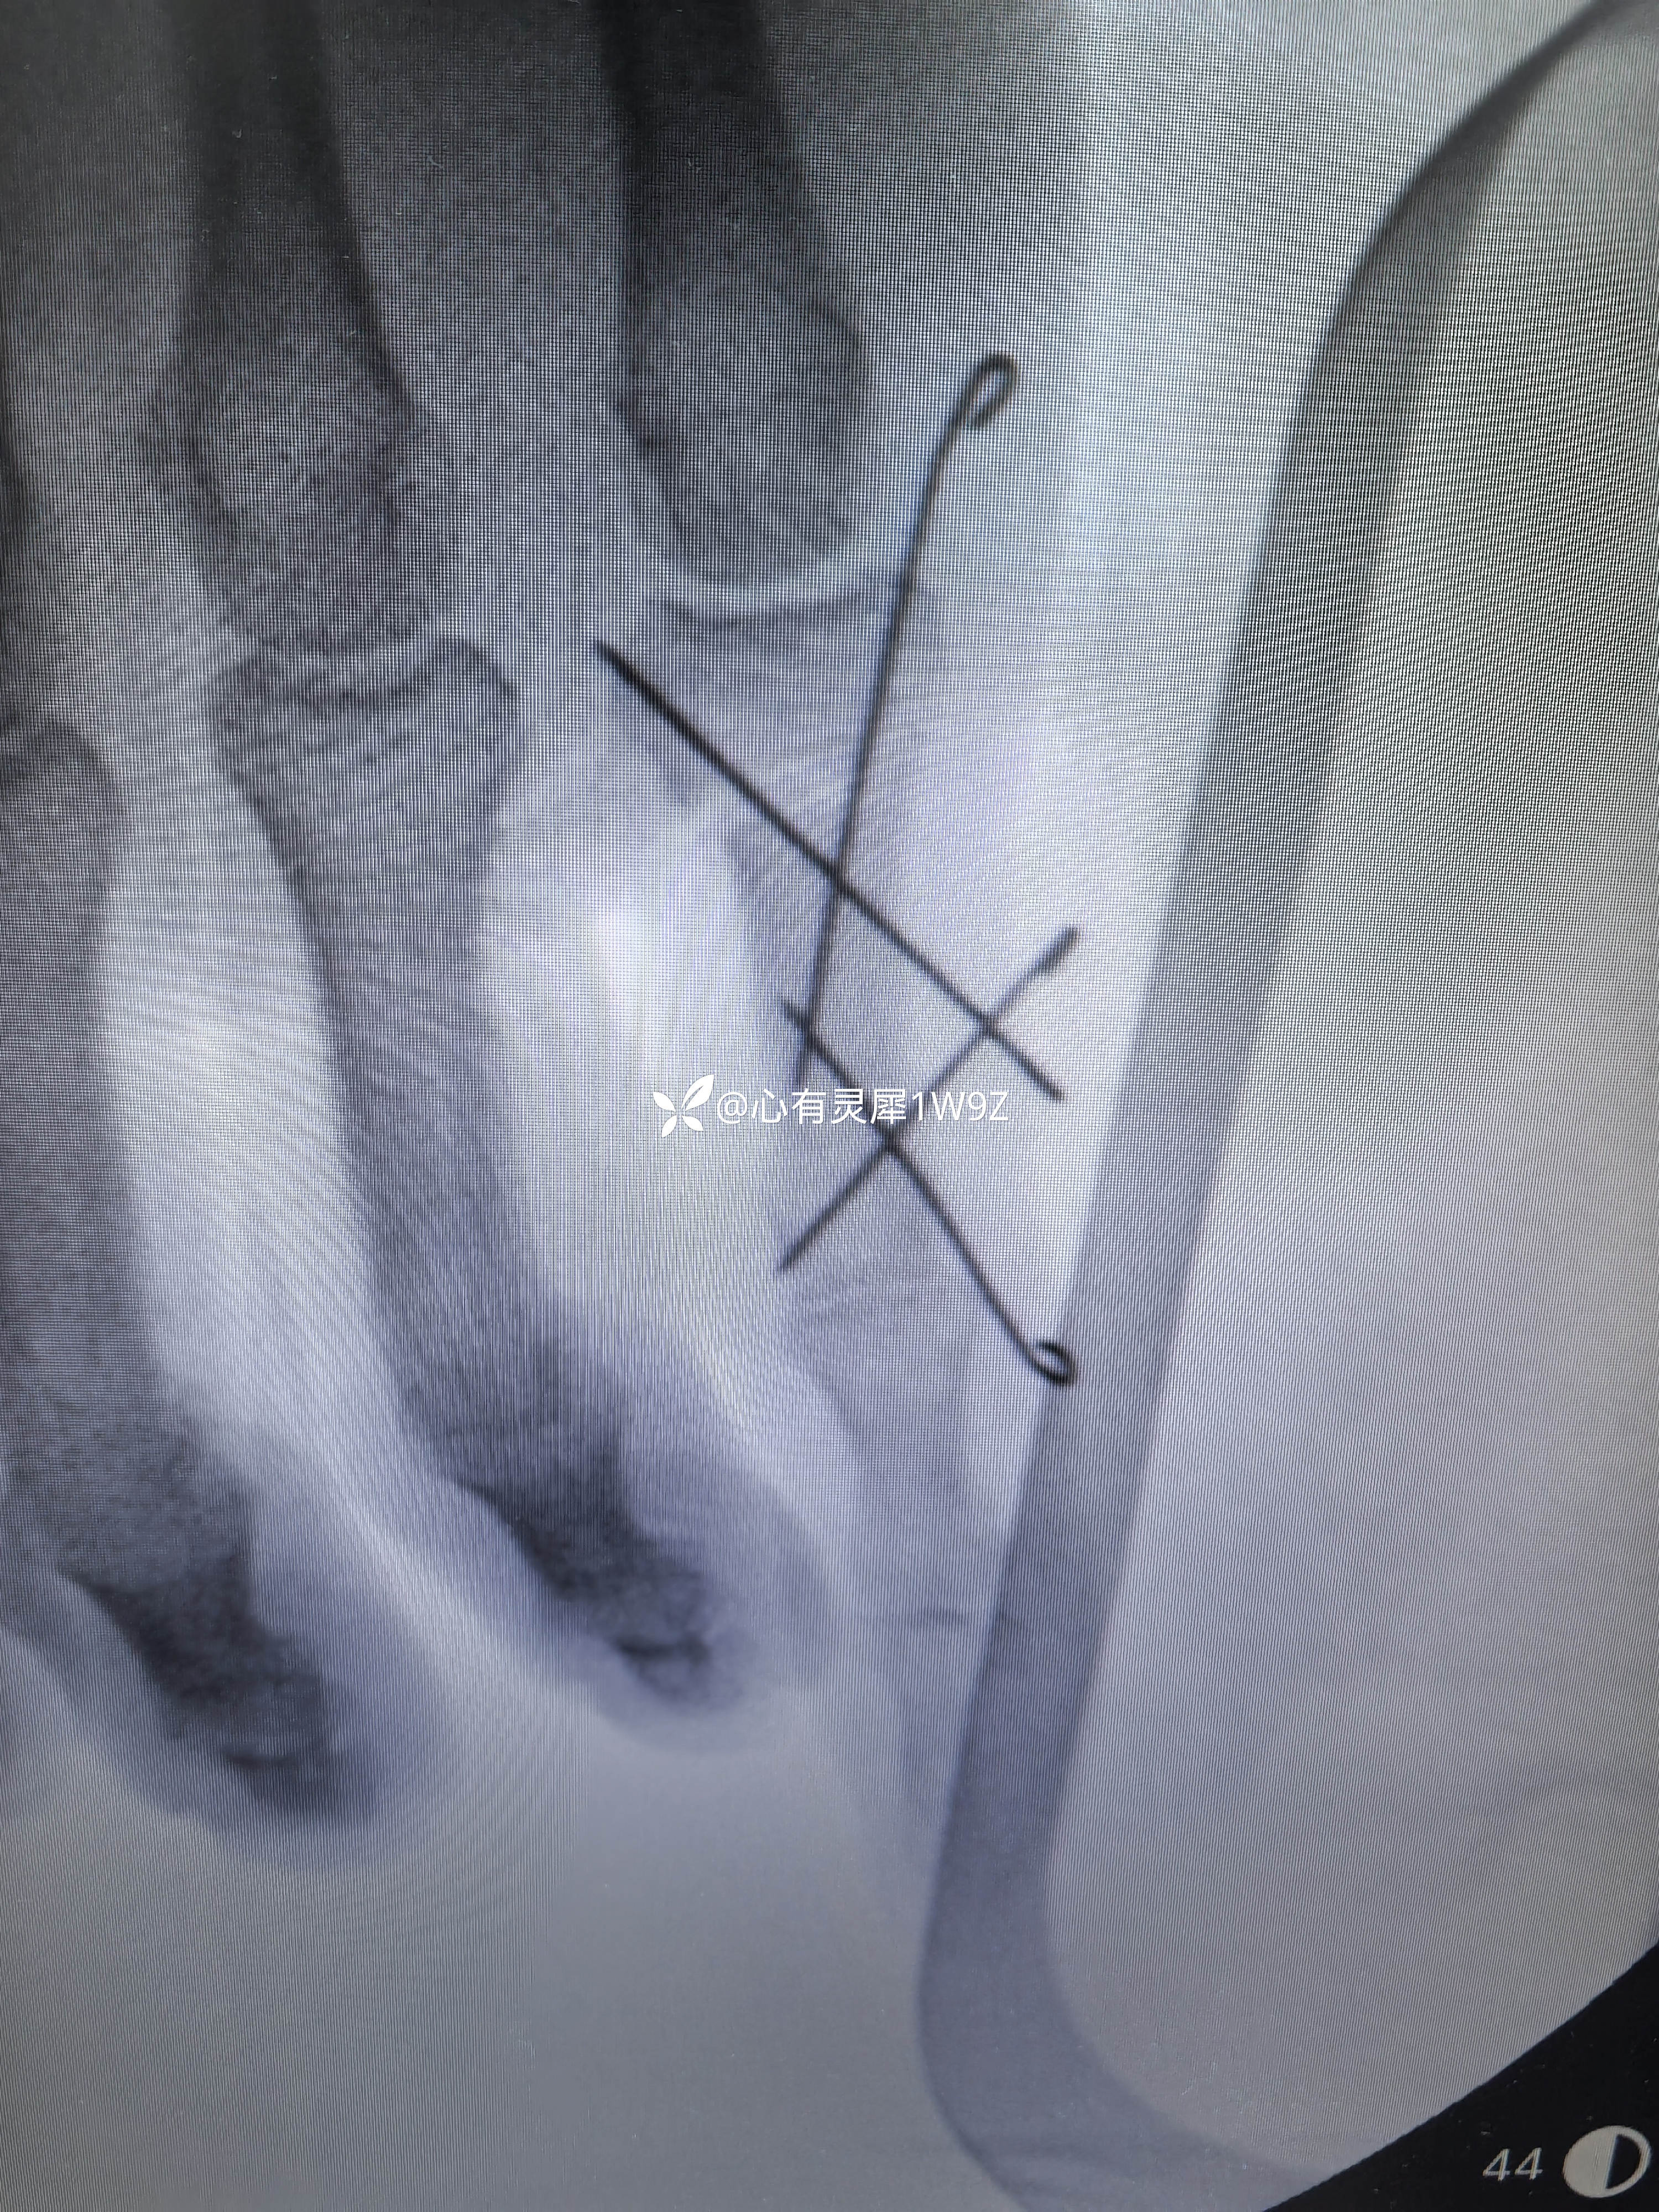

小指近节指骨两处骨折

【治疗经过及结果】:

1.如何设计克氏针固定方案更合理2.术后需要石膏辅助固定吗?3多长时间开始小指屈伸锻炼?4多长时间拔针,一次拔针还是分两次拔针?